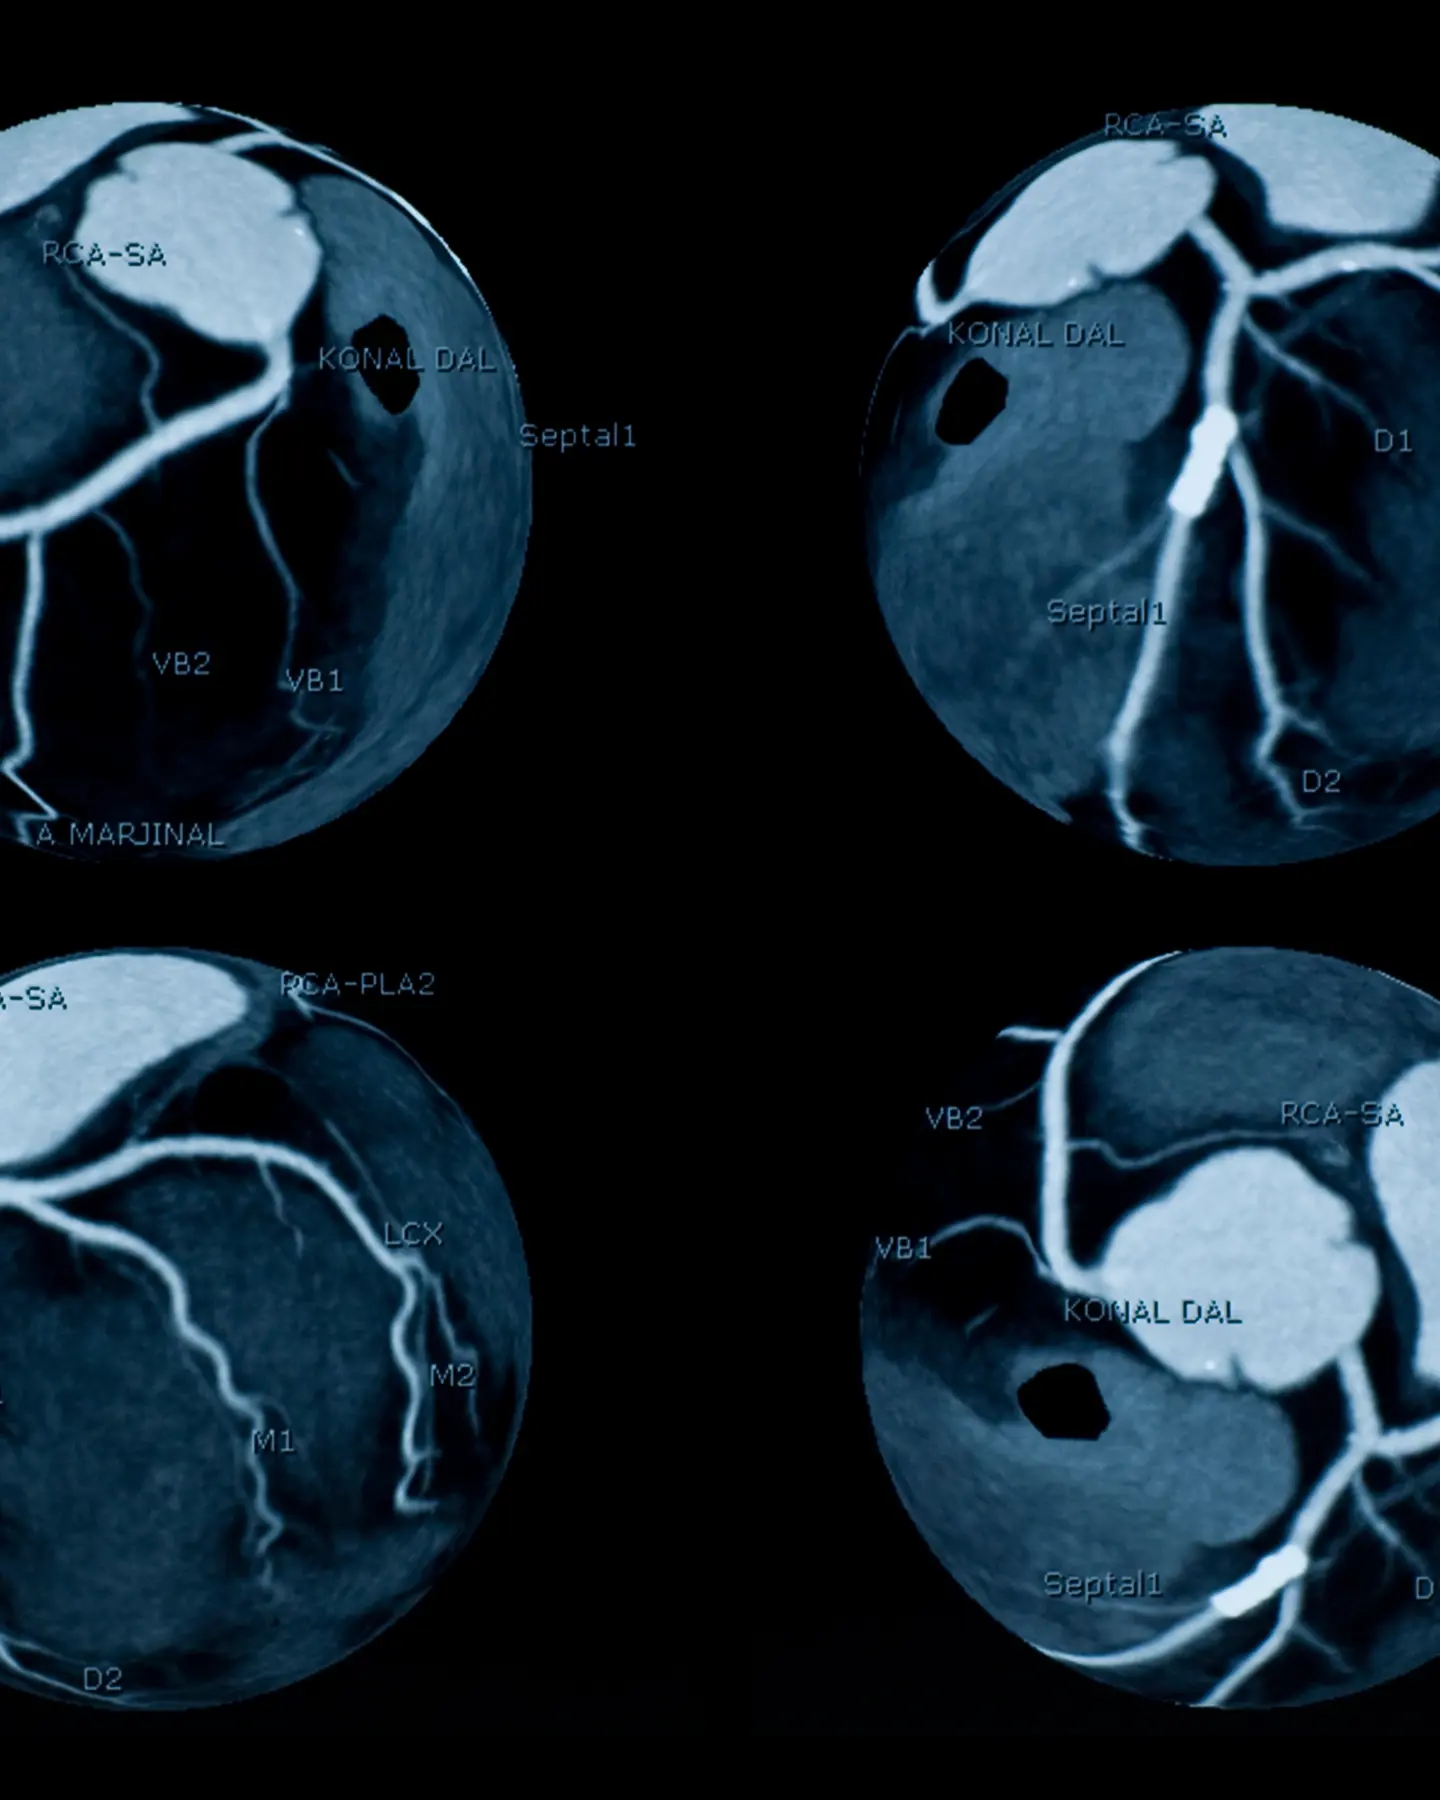

A cardiac CT scan is a non-invasive imaging technology that uses X-rays to create detailed images of your heart and its blood vessels. The images are captured from different angles and then stitched together by a computer to form a 3D picture.

This allows your doctor to check the health and structure of your heart, including its four chambers, muscle, valves, the protective sac that it sits in (pericardium) and its major blood vessels.

A cardiac CT scan can also look for calcium build-up in your coronary arteries. This is a sign of coronary artery disease that can be picked up even before you notice any symptoms, giving you the chance to take the right steps to protect your heart from further damage.